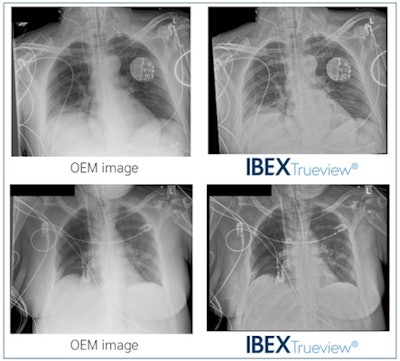

Ibex Trueview is AI software designed to accurately correct for scatter, delivering grid-like diagnostic images with enhanced visibility of tubes and lines in the same contrast stretch, without using a grid, the company said.

Examples of postprocessed enhanced OEM and Trueview images. Images courtesy of Acta Radiologica.In the study, a total of 30 chest x-ray exams were processed using Trueview and compared with standard OEM images by two radiologists and four ICU doctors. Reviewers were more likely to score Trueview higher than OEM for mediastinal structures, bones, retrocardiac region, tube visibility, and tube safety (p < 0.01), according to the findings.

In addition, clinicians were 3.8 times more likely to agree that safe placement of lines and tubes could be confirmed with Trueview images when compared with OEM images.